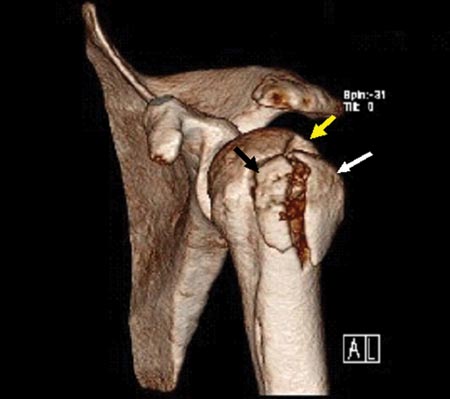

Figura 1A: Fractura con desplazamiento del troquiter mayor a 5 mm./ Figura 1B: Misma fractura en TAC 3D. Conminuta a 3 fragmentos y desplazada. Flechas: fragmentos óseos.

Presentamos 10 pacientes con fracturas desplazadas y/o conminutas del troquíter tratadas por artroscopía entre los años 2004 y 2009, se incluyeron 6 pacientes con fracturas del troquíter a uno o dos fragmentos con desplazamiento mayor a 5 mm y 4 pacientes presentaron fracturas conminutas. En todos ellos se realizó reducción y osteosíntesis por vía artroscópica asistida con radioscopia. Como medio defijación se utilizó, en todos los casos, tornillos canulados de 3.5 y 4.5 mm. Al momento del ingreso, todos los pacientes fueron evaluados con estudios radiográficos de frente en rotación externa e interna y axial y con tomografía axial (TAC) con reconstrucción tridimensional. Estudios por Resonancia Magnética solo fueron realizados en 6 casos. En este estudio se utilizaron las imágenes radiográficas e imágenes por TAC, con reconstrucción en 3D, con el propósito de evaluar el tipo de fractura, grado de desplazamiento, cantidad y tamaño de los fragmentos óseos. Los pacientes con fracturas del troquíter con desplazamiento de fragmentos óseos menor a 5 mm fueron excluidos de este estudio. Los mismos recibieron tratamiento conservador.

Realizado el diagnóstico de lesión articular asociada se examina la fractura a nivel subacromial. Es importante realizar un correcto diagnóstico tomográfico para definir el patrón de la fractura y la ubicación de los fragmentos.